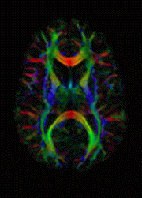

DNA damage, due to environmental factors and normal metabolic processes inside the cell, occurs at a rate of 1,000 to 1,000,000 molecular lesions per cell per day. A special enzyme (shown above in color), encircles the double helix to repair a broken strand of DNA. Without molecules that can mend DNA single strand and double strand breaks, cells can malfunction, die, or become cancerous. (Photo: Courtesy of Tom Ellenberger, Washington University School of Medicine in St. Louis)

Diffusion MRI Diagnostics: Diffusion tensor imaging color map (Photo: Wikipedia)